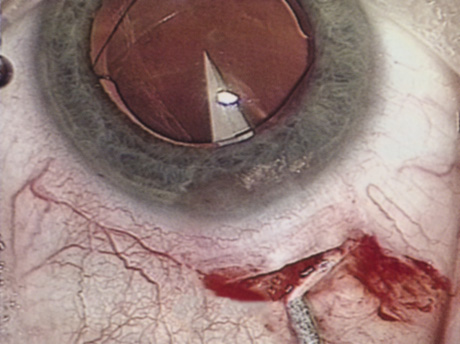

A mature cataract precludes visualization of the fundus. A B-scan ultrasonographic examination provides a real-time, two-dimensional (2D), cross-sectional image of the globe along the marked axis of the probe (Fig. 3). Cataracts are more common in patients with chronic retinal detachment, prior trauma, or intraocular tumors; therefore, a B-scan study is helpful in excluding structural posterior segment pathology before surgery on a mature cataract. Although a negative result to B-scan evaluation is reassuring, the surgeon should remember that it does not predict postoperative visual outcome. The B-scan can be thought of as a picture of Cincinnati from an airplane; the office buildings may all be standing, but you cannot tell whether the people in them are working.